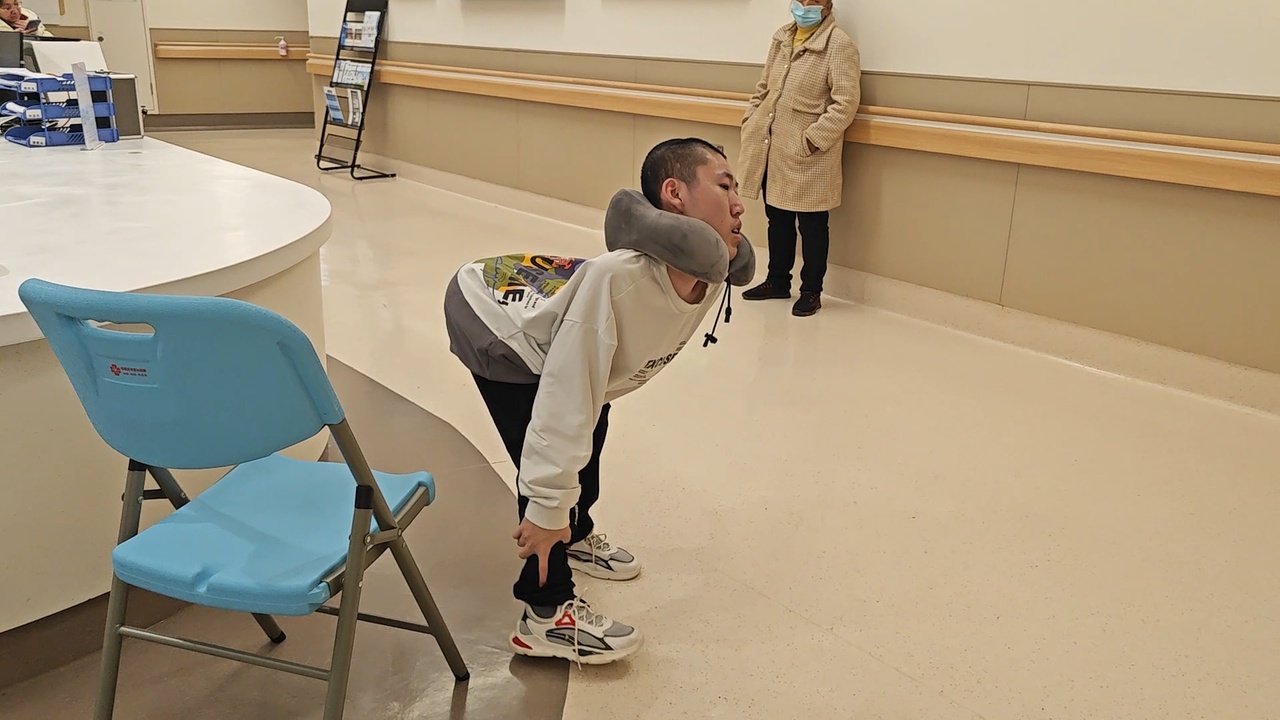

团队为患者设计了严谨的治疗方案,先后完成了反向截骨矫形手术、颈椎截骨矫形翻修手术、髋关节松解手术、胸椎段矫形手术,分4次手术为患者矫正脊椎约170度。患者接受手术后仍需进行康复训练,才能逐步康复。

为此,康复治疗师杨潇为患者定制了个性化训练方案,包括借助沙袋仰卧推胸增肌、用弹力绳辅助踢腿、靠墙加压做俯卧撑等。呼吸训练则借助气球、吸管、激励式肺量计、阈值负荷呼吸训练器等工具辅助患者重建呼吸模式、强化呼吸肌力、增加肺活量。

据了解,该患者已经可以在助行器的辅助下独立行走,活动过程中其呼吸与心率适应性良好。